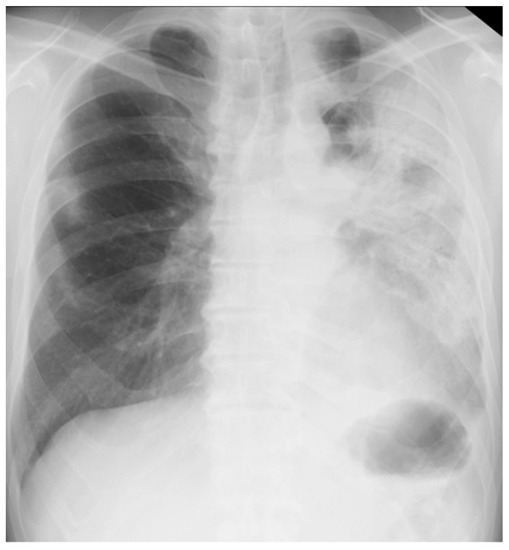

On arrival at our hospital, his blood pressure, pulse rate, and oxygen saturation were normal; however, his body temperature was 37.7 °C. The patient’s respiratory rate was 18 breaths/min. Chest auscultation revealed coarse crackles throughout the left lung field. A chest X-ray showed consolidation in the left lung field. (Figure 3) A chest CT scan showed consolidation in the entire left lung field and leftward deviation of the mediastinum, due to contractile changes. A small area of consolidation was seen just below the peripheral pleura in the right upper and middle lobes. (Figure 4) His blood tests showed leukocytosis (18,300/μL), eosinophilia (26.5%), and high C-reactive protein levels (18.12 mg/dL). KL-6 and SP-D levels were normal. Tests for beta-D-glucan, aspergillus antigen, interferon-gamma release assays, antineutrophil cytoplasmic antibody, antinuclear antibody, anti-aminoacyl-tRNA synthetase antibody, Anti-Scl-70 antibody, and anti-cyclic citrullinated peptide antibody were all negative. The PCR test for coronavirus disease 2019 was negative.

Figure 4. Chest computed tomography of a 59-year-old man with dyspnea scan showed consolidation in the entire left lung field and a leftward deviation of the mediastinum due to contractile changes. A slight consolidation was seen just below the peripheral pleura in the right upper and middle lobes.